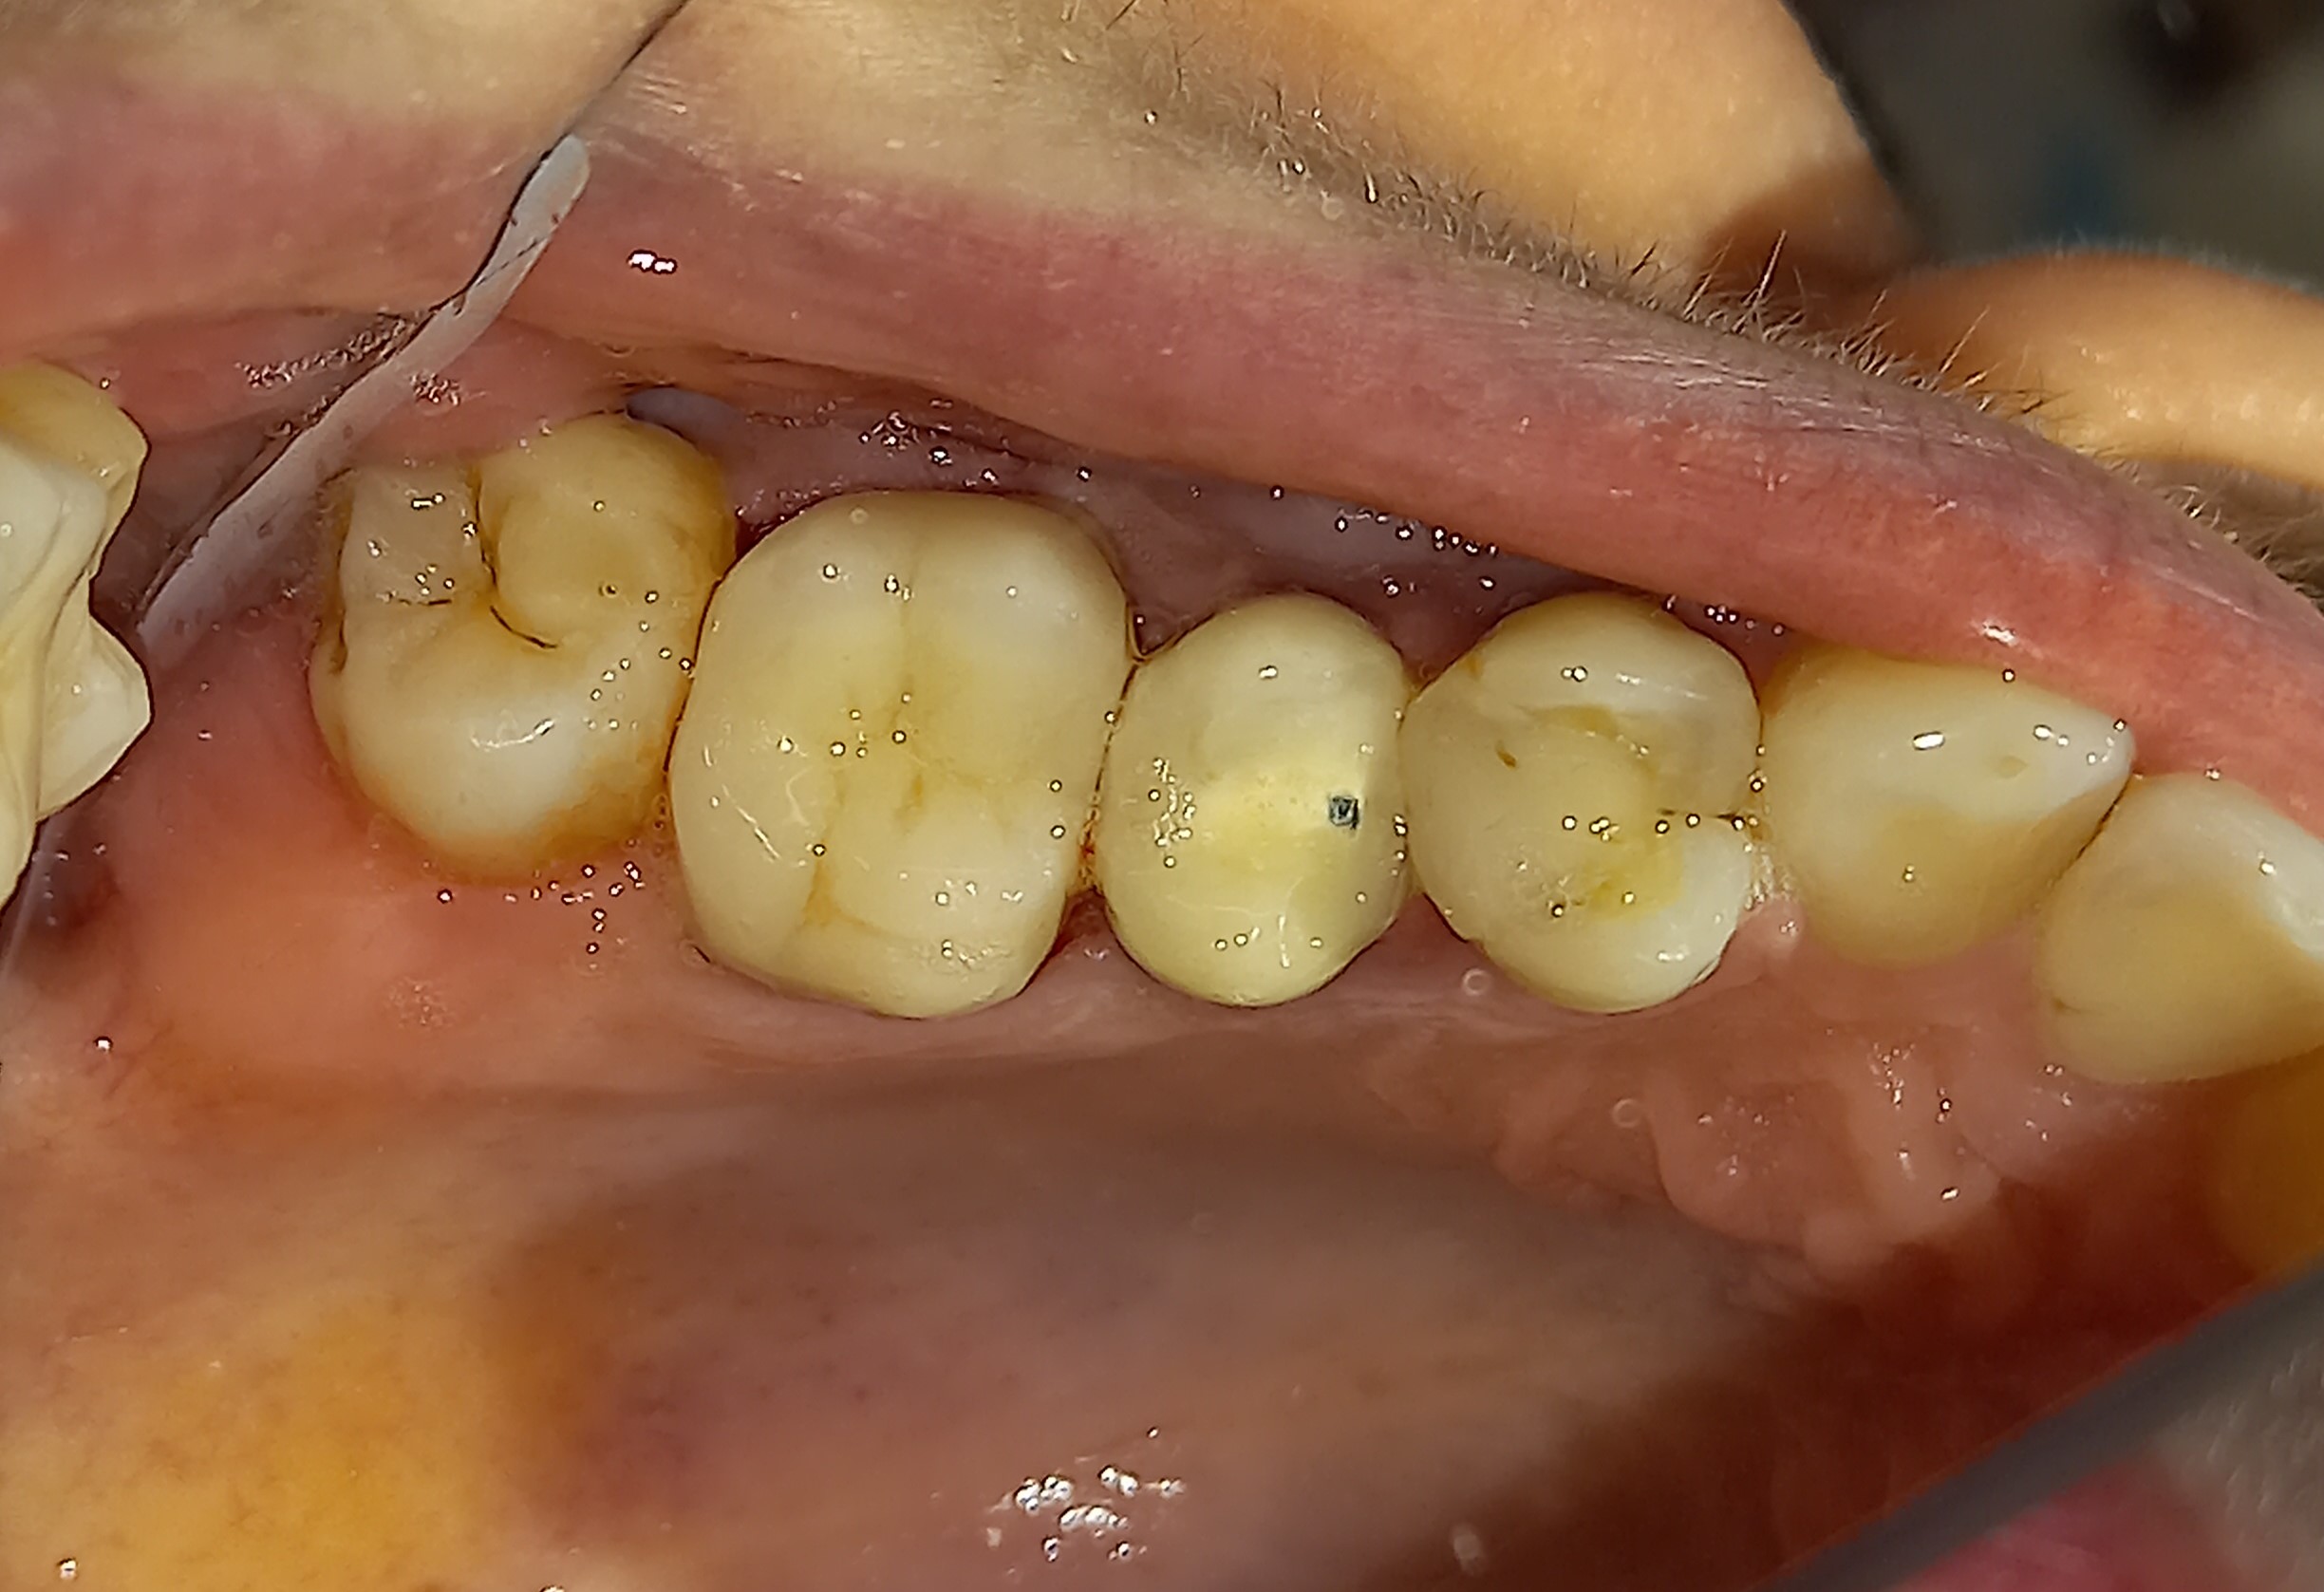

Αρχική εικόνα του παλιού μεγάλου σφραγίσματος

Κλινική εικόνα του μεγάλου οδοντικού ελλείμματος μετά την αφαίρεση του παλιού σφραγίσματος

Το ολοκεραμικό ένθετου στο εκμαγείο από τον οδοντοτεχνίτη

Τελική κλινική εικόνα του ολοκεραμικού επένθετου στο γομφίο